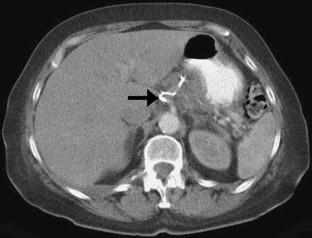

Ruptured Left Gastric Artery Aneurysm: Unique Presentation with Hemothorax and Hemomediastinum

Although splanchnic artery aneurysms are uncommon and remain mostly asymptomatic, they are associated with a high mortality rate when they rupture. We discuss the case of a 66-year-old woman who had successful embolization of a left gastric artery aneurysm after presenting with acute chest pain and the unusual computed tomography findings of hemothorax and hemomediastinum. To our knowledge, only one other similar case has been published in the literature.

Figure 1

Figure 2

Figure 3

Figure 4